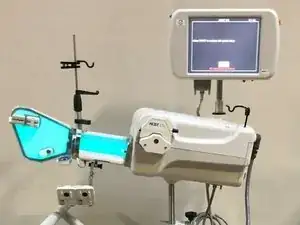

Medical imaging is the process of creating visual representations of the internal structures of the body beneath the skin and bones. These images can then be used for clinical analysis, diagnosis and discovery of abnormalities, and to create plans for medical intervention. Medical imaging uses a variety of technologies based on the area of analysis, including but not limited to “X-ray radiography, magnetic resonance imaging, ultrasound, endoscopy, elastography, tactile imaging, thermography, medical photography, and nuclear medicine functional imaging techniques as positron emission tomography (PET) and single-photon emission computed tomography (SPECT).” (Wikipedia)